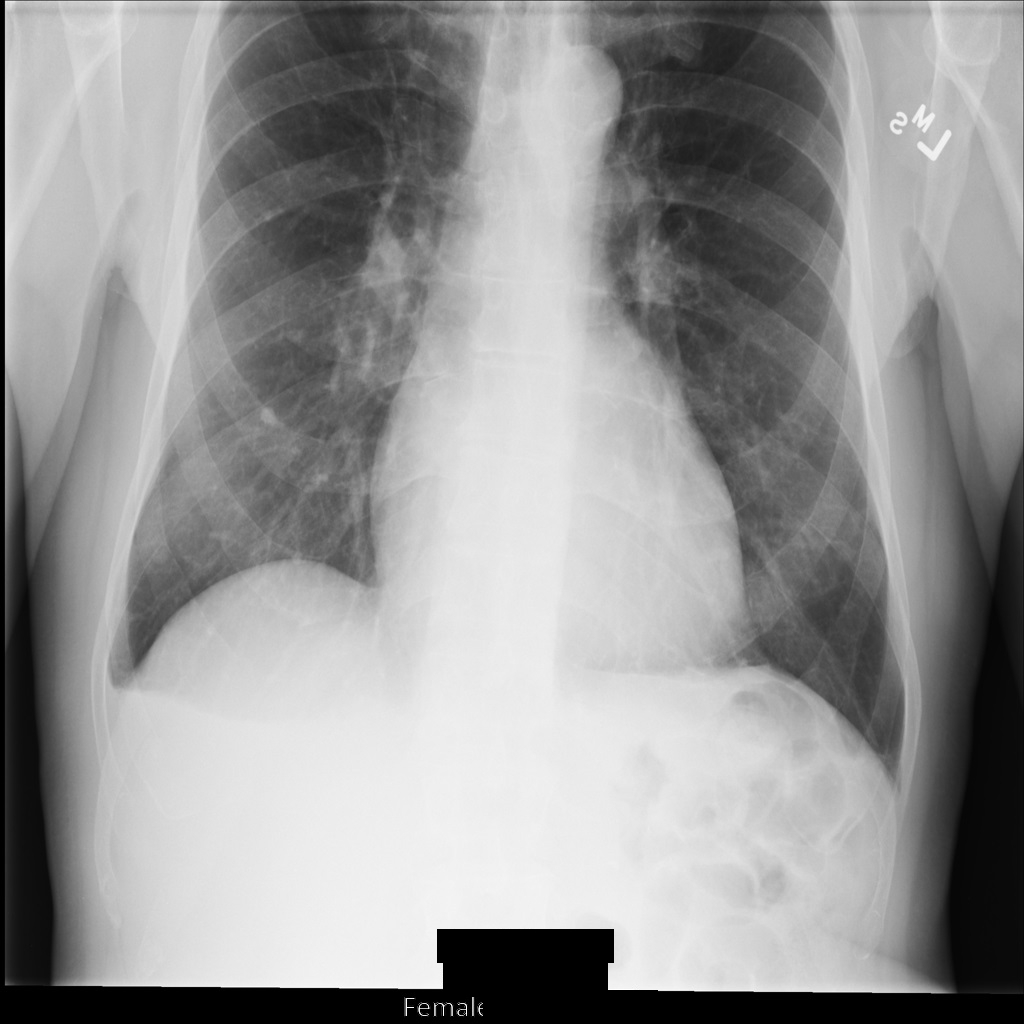

Après avoir anonymisé l'image à l'aide de REDACT_ALL_TEXT

, elle se présente comme suit. Notez que tout le texte incrusté en bas de l'image a été masqué.

REDACT_ALL_TEXT